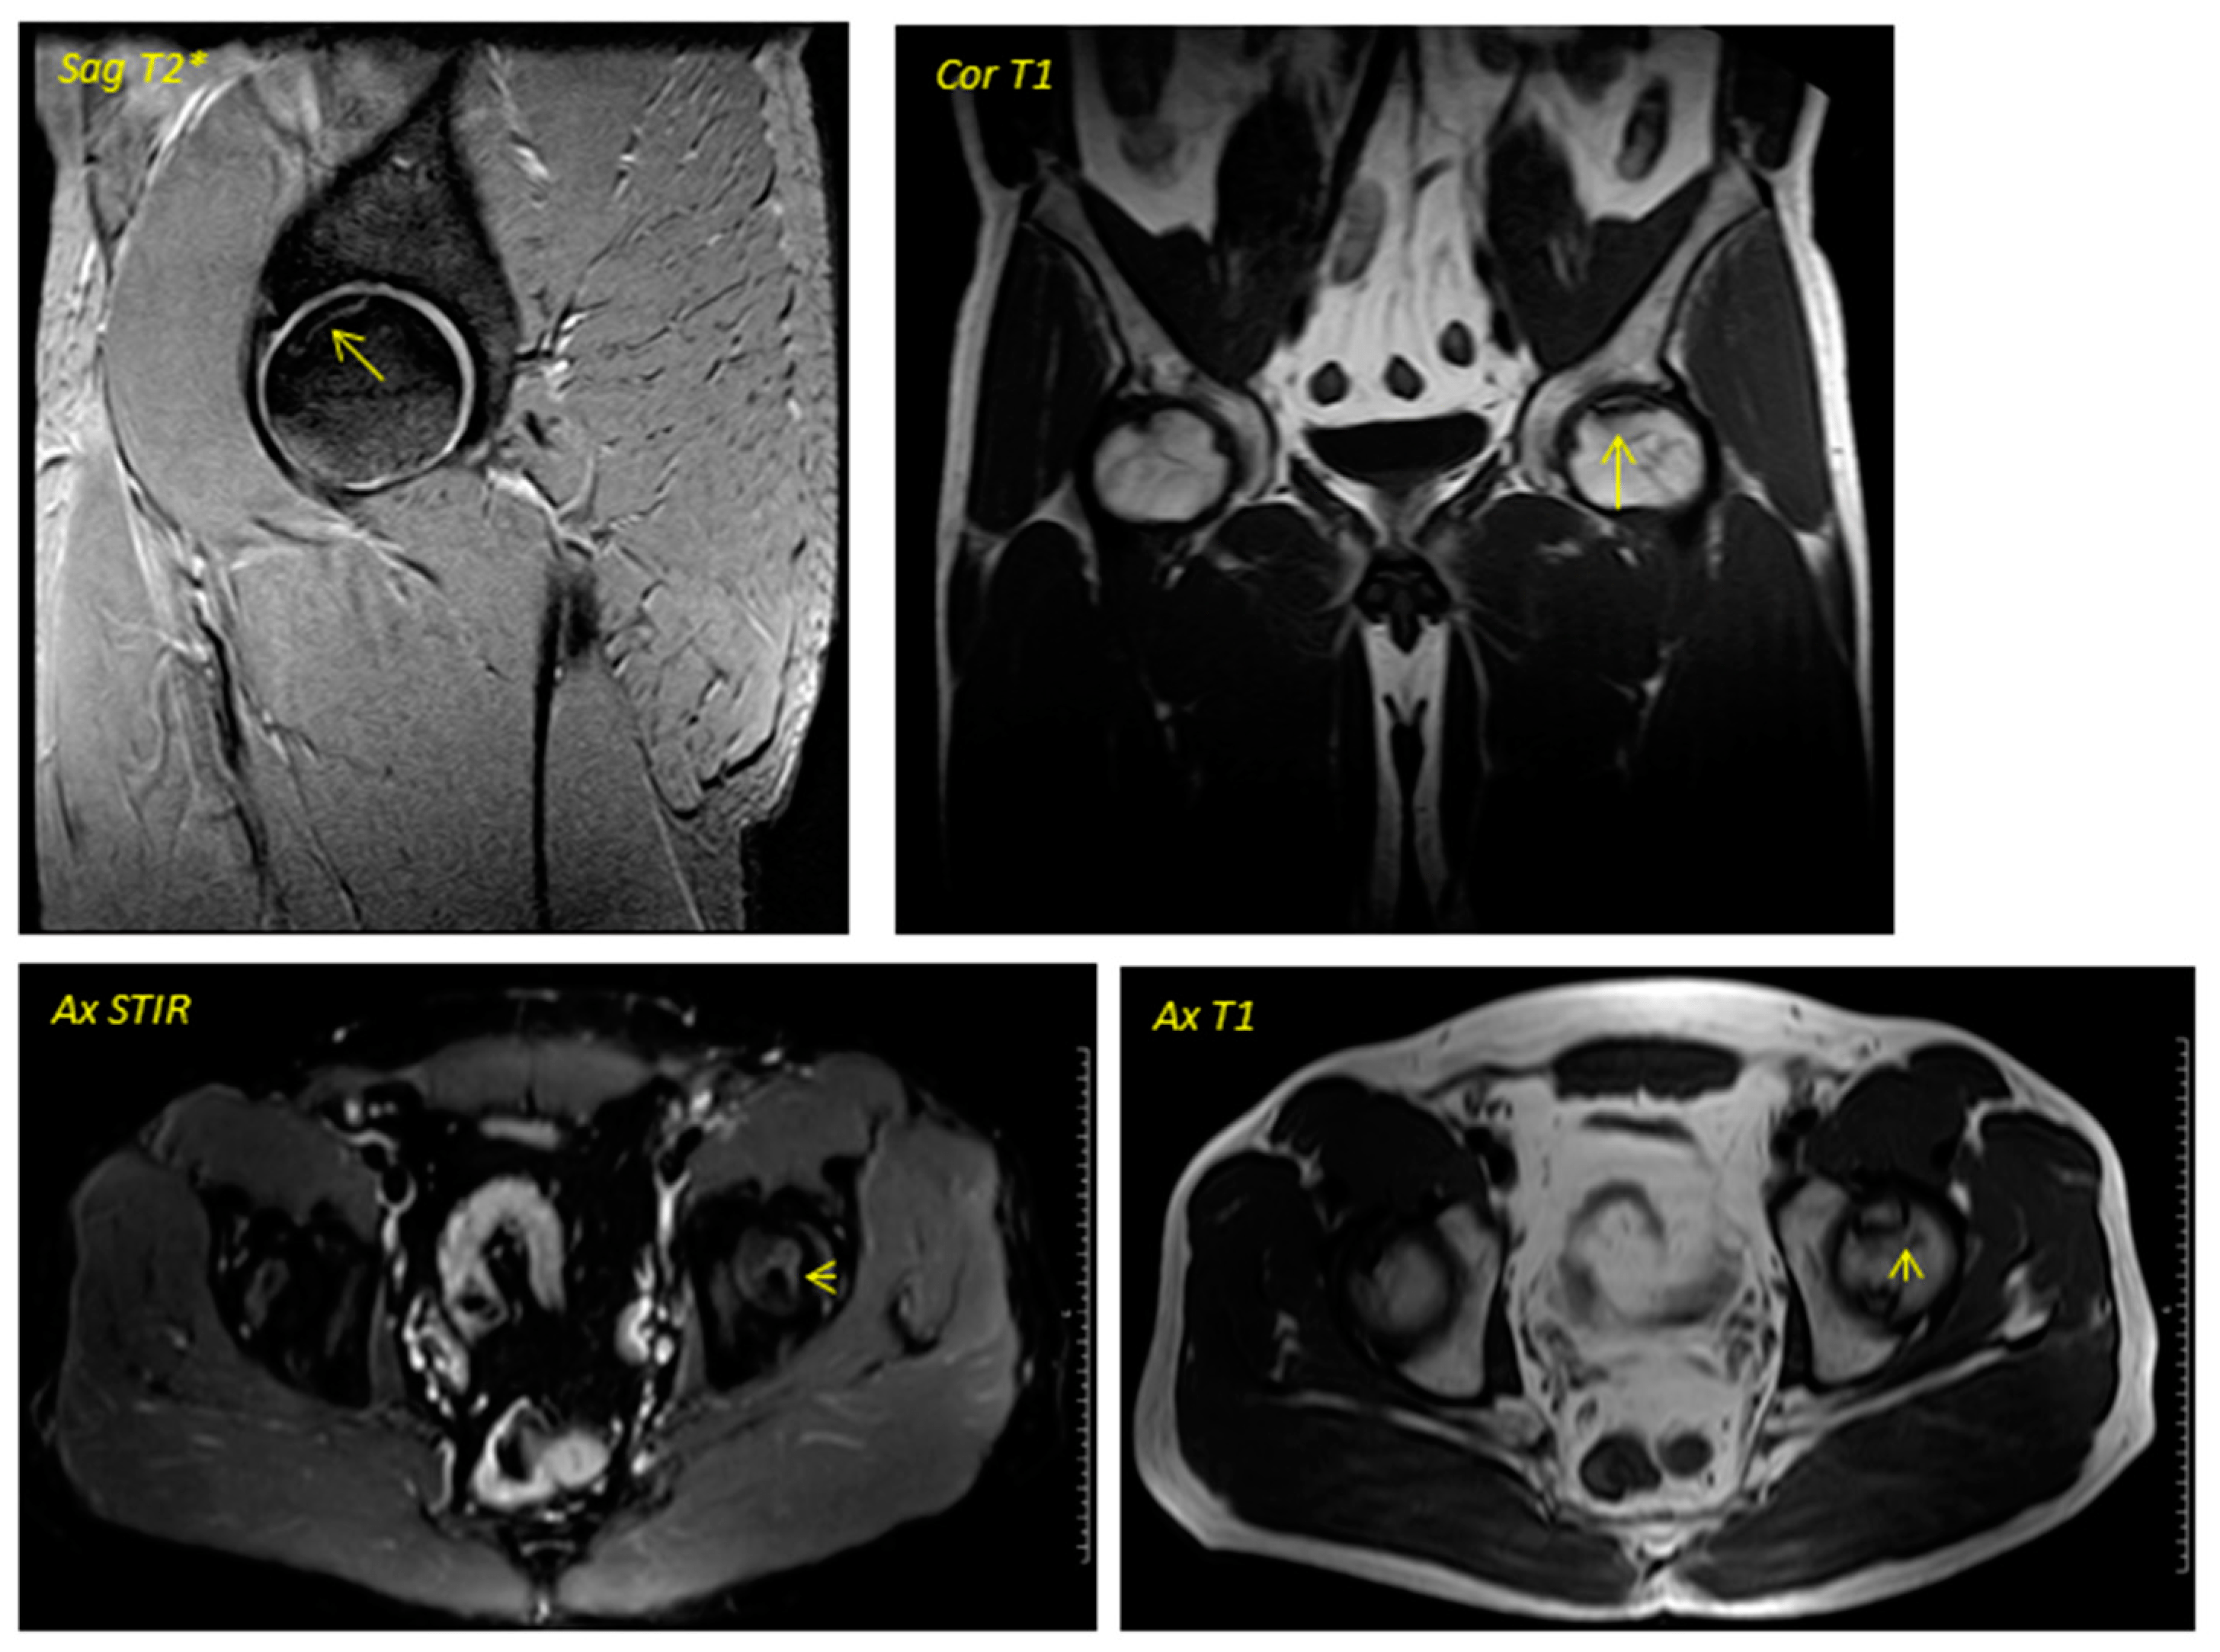

關(guān)于影像學研究,在12個月的隨訪期間,在影像學演變中觀察到了一些發(fā)現(xiàn)(圖1和圖2)。

首先,方向的變化從第六個月開始出現(xiàn)在所有病例中,而在早期階段并不明顯。其次,62.5%的患者 ( n=5) 在手術(shù)后的第一年內(nèi)實現(xiàn)了影像穩(wěn)定。第三,兩名患者 (25%) 出現(xiàn)壞死區(qū)進展,而一名 (12.5%) 患者出現(xiàn)明顯的再骨化跡象。盡管觀察到描述性差異,但后一個參數(shù)的p值在統(tǒng)計學上并不顯著。